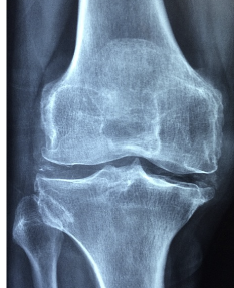

무릎은 우리 몸의 대형 관절 중 하나로 다리의 무게 중심을 지탱하고 보조하여 몸을 서있거나 걷는 등의 동작을 수행합니다. 무릎은 대퇴골과 족골, 무릎뼈가 결합하여 이루어진 관절로, 뼈의 말단 부분은 연골로 되어 있으며, 무릎을 강화하는 인대와 근육으로 둘러싸여 있습니다. 이러한 구조는 무릎을 자유롭게 움직이면서도 안정적으로 지탱하게 해줍니다. 하지만 연령과 스포츠 부상, 비만 등으로 무릎을 손상시키는 경우가 많습니다.

- 연골의 마모 : 무릎 관절엔 연골이 존재하며, 이 연골이 마모되면 무릎이 지지하기 위해 뼈와 뼈가 마찰되어 소리가 발생할 수 있습니다. 연골의 마모는 연령이 들어감에 따라 발생할 수 있으며, 스포츠나 부상 등으로 인해 발생할 수도 있습니다.

- 관절염 : 무릎 관절염은 무릎 관절의 연골이 파괴되거나 마모되어 뼈와 뼈가 마찰되어 소리가 발생할 수 있습니다. 무릎 관절염은 연령이 들어감에 따라 발생할 수 있으며, 과다한 체중과 부상 등이 원인이 될 수 있습니다.

- 퇴행성 관절질환 : 무릎 관절의 뼈와 연골의 변성이나 파괴로 인해 무릎에서 소리가 발생할 수 있습니다. 퇴행성 관절질환은 연령이 들어감에 따라 발생할 가능성이 높습니다.

무릎 연골 마모는 무릎 관절에서 연골이 손상되어 생기는 질환으로, 노화나 과도한 사용 등이 원인이 될 수 있습니다. 증상으로는 무릎 통증, 부종, 불안정성, 걷기나 등산 등 일상생활에서 무릎을 사용할 때 힘든 느낌 등이 있습니다.

무릎 연골 마모는 진행되면서 뼈와 뼈가 마주치기 때문에 더 많은 통증과 불편을 유발할 수 있습니다. 또한 연골의 기능이 손상되면 충격을 흡수하는 능력이 약해져서 무릎 관절에 더 큰 스트레스가 가해져 다른 문제가 발생할 수도 있습니다. 따라서 무릎 연골 마모는 적극적인 치료가 필요합니다.